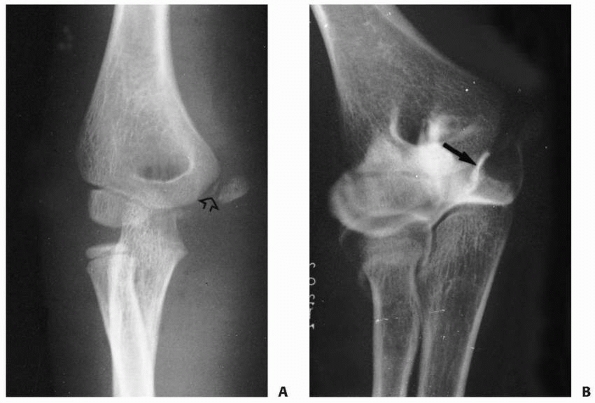

![]() |

FIGURE 15-15 A. A 10-year-old boy with cubitus valgus resulting from a fracture of the lateral condylar physis with nonunion. B.

Nonunion with cubitus valgus. Radiograph showing both angulation and translocation secondary to nonunion of the condylar fragment. |

FIGURE 15-16

Nonunion without translocation. Milch type I fracture pattern. Despite nonunion, elbow stability was maintained because the lateral crista of the trochlea had remained intact (arrow). Valgus angulation also developed. |